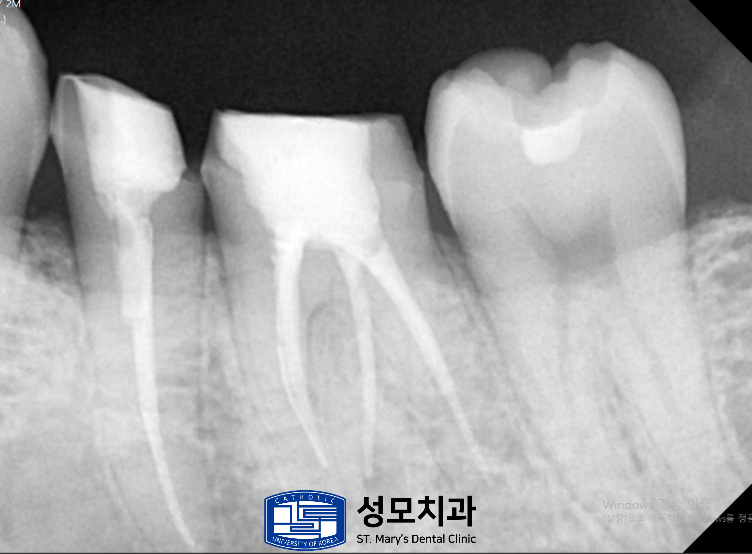

왼쪽 위아래에서는 내부 코어까지만 형성된 상태로

최종 보철이 미완성인 치아 두 개가 확인되었는데요.

코어까지만 형성된 채로 방치되어 있던

두 치아는 남은 치질의 두께를

재평가한 후 최종 크라운을 장착했습니다.

치관의 약 3분의 1만 남았던 치아는

치근 길이, 치주 지지, 치경부

균열 여부를 종합 평가한 결과

보존 치료가 가능하다고 판단했습니다.

근관치료로 감염을 제거하고

코어 빌드업으로 남은 치질을 보강하여

크라운을 안정적으로 지지하게 했습니다.